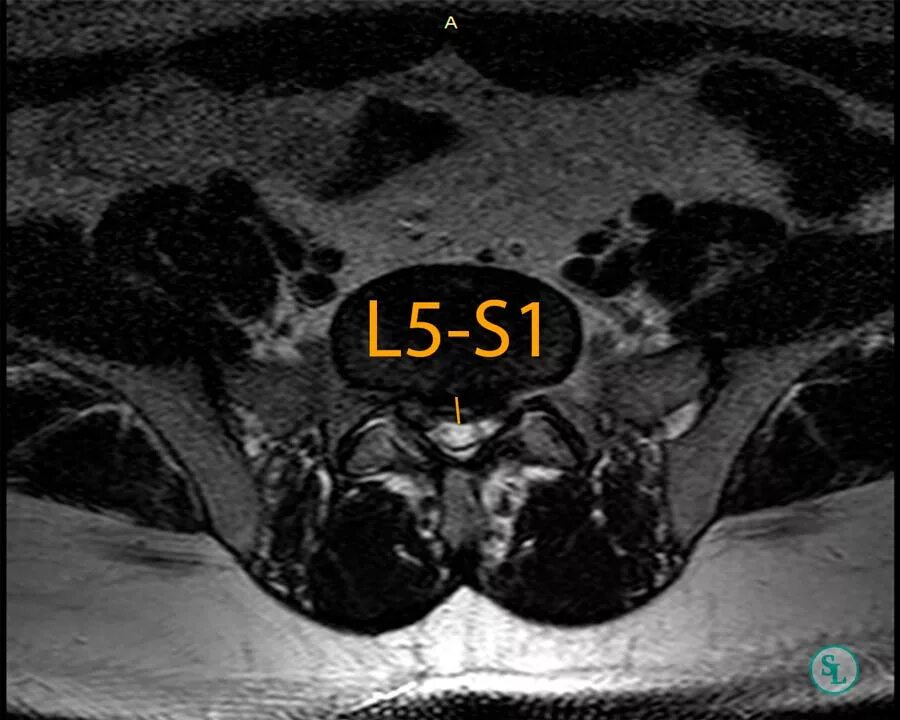

Операция удаление грыжи l5 s1